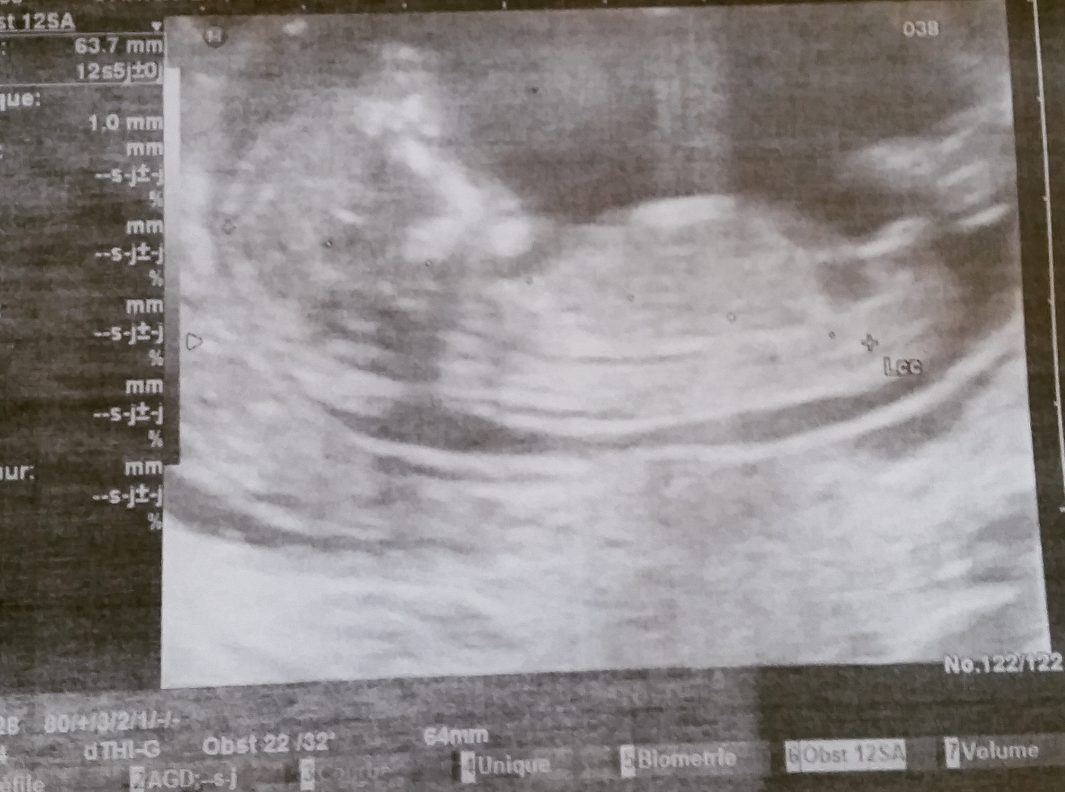

Moi là comme ça je dirai filles... L'avantage c'est que t'as pas longtemps a attendre lol.Écho ce matin donc tout va bien pour la trisomie et pour l'instant contrairement à mon fils ou des 12sa il était sur casiment que c'était un garçon la il ne se prononce pas il me dira le mois prochain il m'a dit donc je garde espoir encore pour je fillAfficher la pièce jointe 711891 Afficher la pièce jointe 711892 e lol